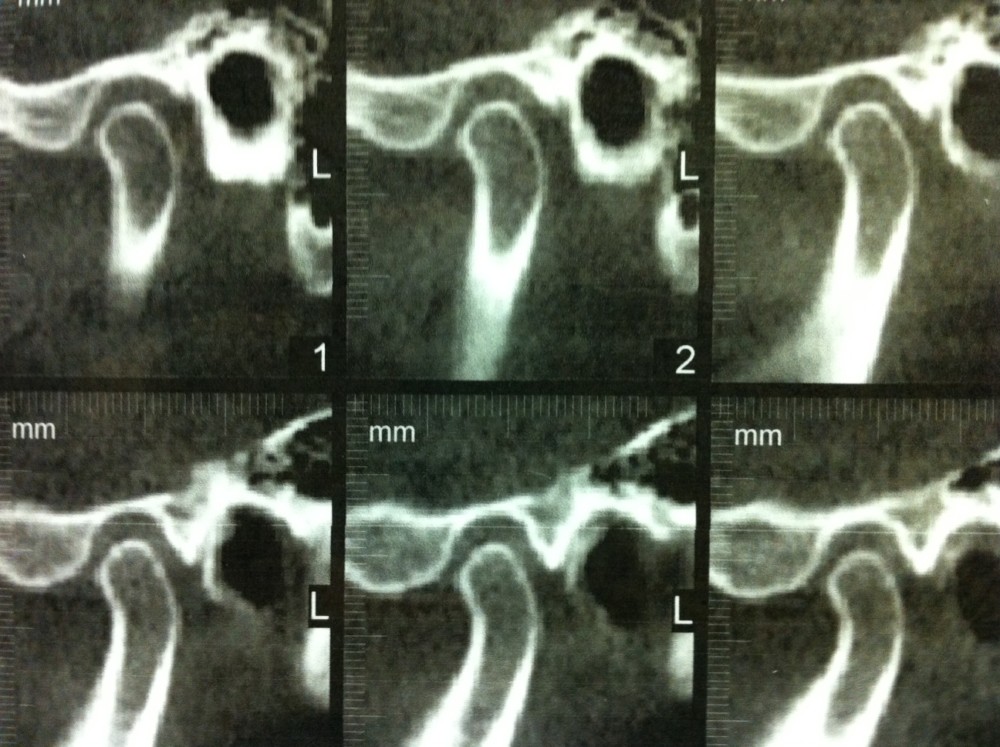

CTImageofTMJ Hobart Orofacial Pain and Special Needs Clinic Can You See Tmj On An X Ray the disc has a low signal on all mri sequences, but it may be possible to see intermediate signal centrally in the anterior and posterior. a variety of modalities can be used to image the tmj, including magnetic resonance imaging (mri), computed. tmj dysfunction (tmd) causes pain and inflammation in your jaw joints. panoramic film of. Can You See Tmj On An X Ray.